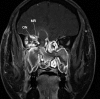

Invasive fungal sinusitis causes painful orbital apex syndrome with ophthalmoplegia and visual loss; the mechanism is unclear. We report an immunocompromised patient with invasive fungal sinusitis in whom the visual loss was due to posterior ischaemic optic neuropathy, shown on diffusion-weighted MRI, presumably from fungal invasion of small meningeal-based arteries at the orbital apex. After intensive antifungal drugs, orbital exenteration and immune reconstitution, the patient survived, but we were uncertain if the exenteration helped. We suggest that evidence of acute posterior ischaemic optic neuropathy should be a contra-indication to the need for orbital exenteration in invasive fungal sinusitis.